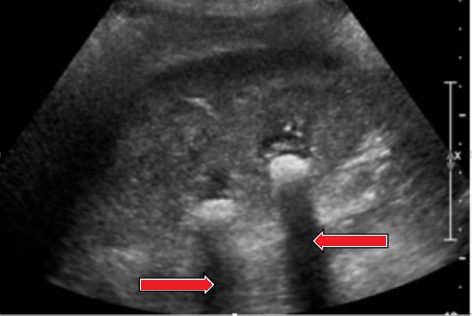

Który artefakt wskazano strzałkami na obrazie USG nerki?

A. Cień akustyczny.

B. Ogon komety.

C. Podwójne odbicie.

D. Wzmocnienie akustyczne.